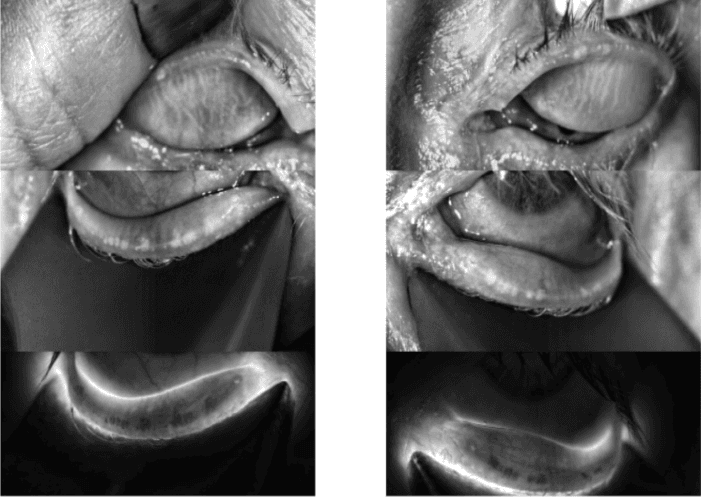

Vectored thermal pulsation specifically refers to one commercial instrument (LipiFlow; Johnson & Johnson, Jacksonville, FL) that simultaneously produces heat on the inner surface of the upper and lower eyelids, combined with automated externally vectored and pulsed pressure to target obstructed meibomian glands.

Two other devices in the category of in-office thermal systems (TearCare, Sight Sciences, Inc, Menlo Park, CA & iLux, Alcon, Forth Worth, TX) heat the outer eyelids but require manual application of pressure.48 All of these devices work by heating the inner or outer eyelid surface to a temperature sufficient to melt meibum. The practitioner then expresses the meibum to fully evacuate the gland contents.